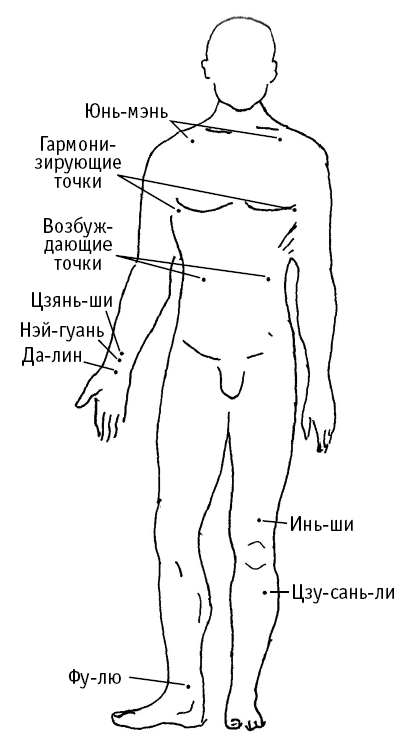

Юнь-мэнь («ворота облака») расположена на груди, в подключичной ямке (между большой грудной и дельтовидной мышцами), кнаружи от грудной срединной линии.

Гармонизирующие точки расположены на груди по бокам от сосков. Используются при гипертонии.

Возбуждающие точки расположены в подреберье – на расстоянии в ширину ладони от срединной вертикальной линии туловища.

Инь-ши («город болезнетворного холода») расположена на 3 цуня выше надколенника (или на 6 цуней выше нижней точки колена), кнаружи от срединной линии ноги.

Цзу-сань-ли («нога» и «селения, расположенные на проезжих путях») расположена на 3 цуня ниже колена, на 1 цунь кнаружи от середины голени.

Фу-лю («возвратное стремительное течение») расположена у переднего края пяточного сухожилия.

Да-лин («большой холм») расположена посередине лучезапястной складки руки.

Цзянь-ши (считается успокаивающей ТОЧКОЙ ПЕРИКАРДА, наружной оболочки сердца) расположена на 3 цуня выше лучезапястной складки, сгиба запястья.

Нэй-гуань («внутренний горный проход») расположена на 1,5 цуня выше лучезапястной складки (положите на запястную складку указательный и средний палец – их общая ширина отмерит 1,5 цуня).